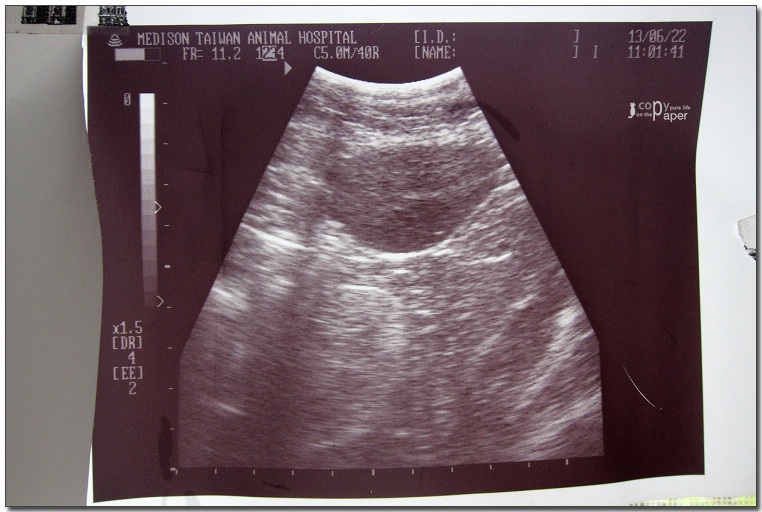

照了X光,

做了超音波,

體重6.4公斤(明明瘦瘦的,怎麼那麼重?),

好像沒什麼大礙,

打了2針,

又拿了二星期的藥,

買了化毛膏。